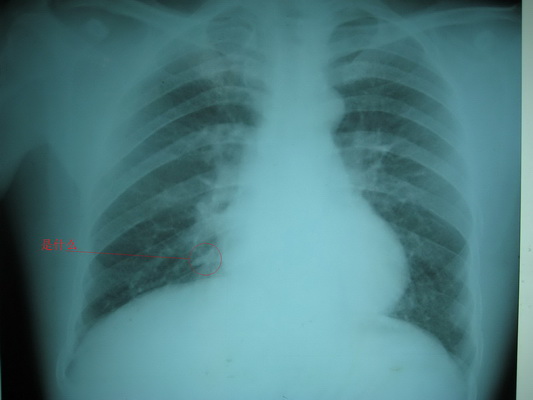

标题: X5931:男,45岁.水泥厂工人体检. [打印本页]

标题: X5931:男,45岁.水泥厂工人体检.

密度挺高,看走形像肋软骨钙化。

条件偏小,胸膜钙化?

盘状肺不张?

右下胸膜钙化?建议必要时行ct扫描检查。

底段血管

支持血管影,血管及周边组织组合影

两肺纹理增粗,两肺门稍增大,结合临床考虑尘肺改变可能.右下肺心隔角旁条索影应该是右下肺静脉影.

不除外感染或肺不张,ct不就行了